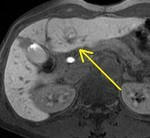

[画像診断]第17回肝血流動態イメージ研究会 Gd-EOB造影肝細胞相で集積増加するHCCについて 2011-03-01